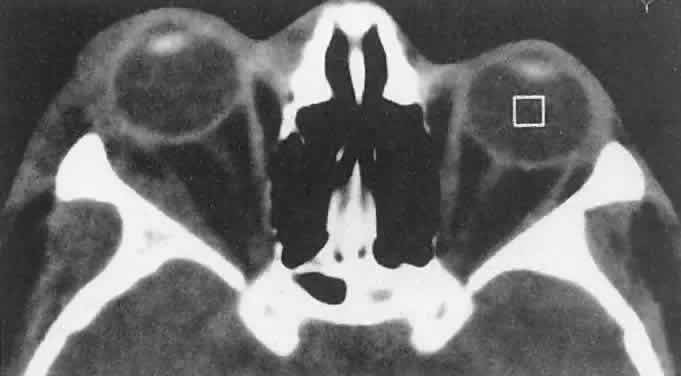

The depth of involvement determines the clinical appearance. The most superficial lesions occur in the dermis or superficial subcutaneous tissues, producing the typical cherry or strawberry appearance. These lesions represented 25% of cases in the series of Haik and coworkers.65 Because elastin fibers are disrupted over the lesion, skin changes may be irreversible, leaving a crepe-paper appearance after tumor regression. Lesions of moderate depth, which accounted for 68% of cases in the same series, appear more bluish than red. Tumor expansion with crying or other elevation of venous pressure averages approximately 50% and is rarely as dramatic as that noted with orbital varices, which communicate more patently with the systemic venous circulation. Deep orbital tumors (7% of cases) may occur without an anterior, obviously vascular component (Fig. 7A). Rapid growth in these cases raises the specter of a malignant orbital tumor, and diagnostic studies may be required for differentiation.

Fig. 7. A. A 10-month-old girl presenting with an inferior orbital tumor that proved to be a capillary hemangioma. B. CT of this patient shows an inferior orbital tumor mass that has caused generalized expansion of the bony orbit, suggesting chronicity.

CT (see Fig. 7B) shows a homogeneous mass that is not particularly distinct from normal orbital structures. Depending on the growth rate, there may be enlargement of the bony orbit in a smooth, symmetric pattern, a nonspecific finding produced by any lesion that has slowly expanded in the first few years of life. Capillary hemangiomas are soft, compressible lesions that grow without indenting the globe. Intravenous contrast agent enhances the tumor's radiodensity, but this feature does not distinguish the lesion from malignant tumors that may be in the differential diagnosis.

The high contrast sensitivity of MRI allows better delineation of capillary hemangioma from normal structures than does CT. The tumor is hyperintense in T2-weighted images with gadolinium and fat suppression (Fig. 8). Low-intensity streaks represent flow voids within higher flow draining and feeding vessels.